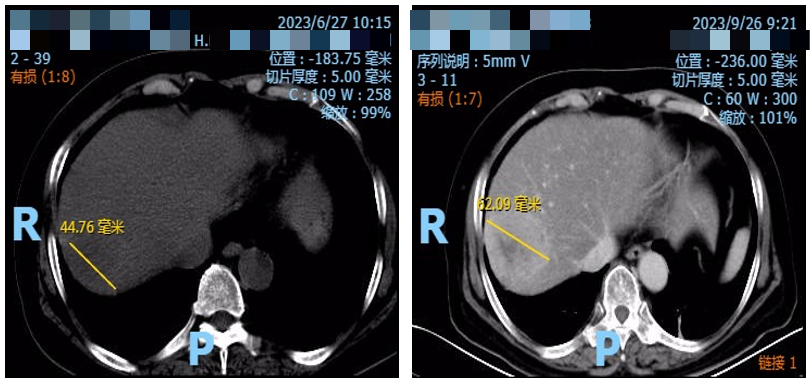

2023年8月10日复查CT示肝脏靶病灶增大至48.77mm(图2)。

疗效评价为疾病稳定(SD),但有进展趋势。

图2. 腹部CT检查(左:2023年6月27日,右:2023年8月10日)

2023年9月26日复查CT示肝脏靶病灶进一步增大至52.09mm(图3)。

疗效评价为疾病进展(PD)。

图3. 腹部CT检查(左:2023年6月27日;右:2023年9月26日)